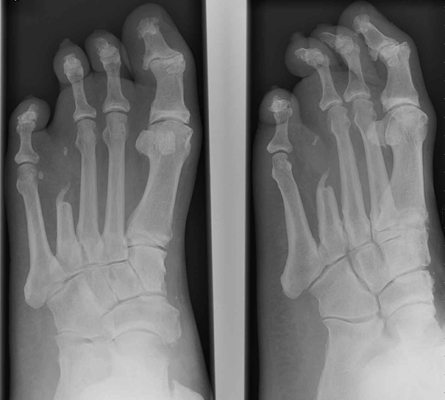

Occasionally because of infection with or without ischemia,

particularly in the diabetic foot and occasionally following trauma, removal of one or

more of the central rays, either partially or completely is indicated.